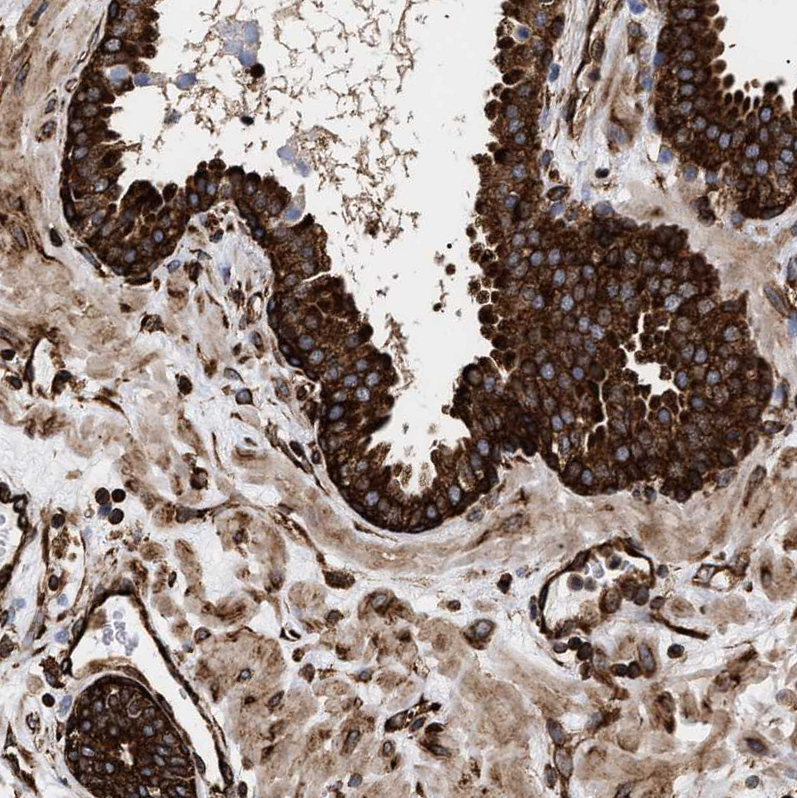

Immunohistochemical staining of human testis shows strong cytoplasmic positivity in cells in seminiferous ducts.